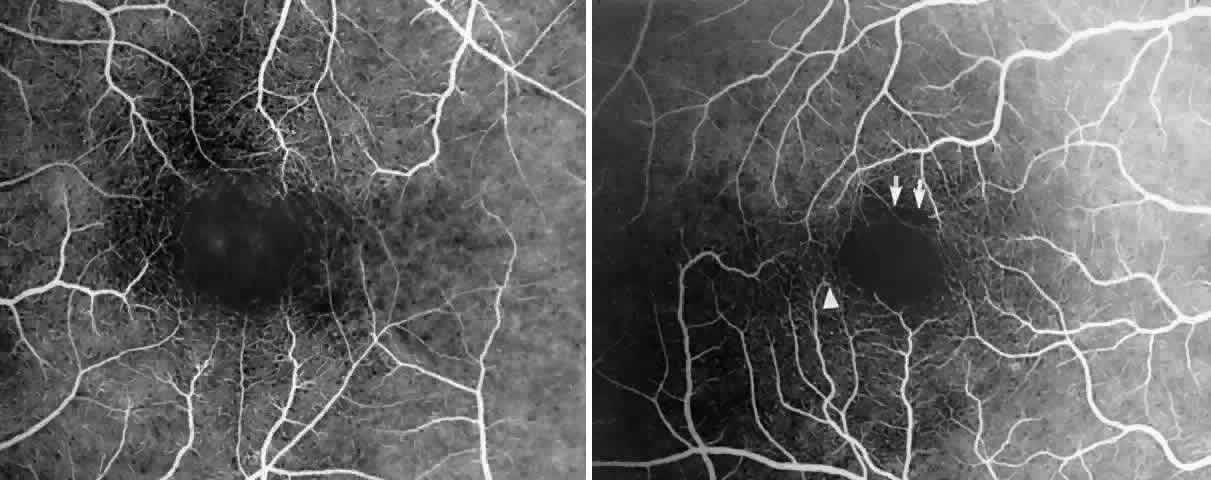

Macular Function Testing in Sickle

Cell MaculopathyThe visual acuity in patients with sickle cell disease is often normal, despite the presence of an enlarged foveal avascular zone or other evidence of sickle cell maculopathy (Fig. 14). In addition, patients with sickle cell maculopathy have a remarkable absence of visual complaints. Although 55% of patients with homozygous sickle cell anemia had abnormal contrast sensitivity, no significant relationship was demonstrated between contrast sensitivity and macular vascular abnormalities.101 Automated visual field analysis has demonstrated significantly larger scotomas in patients with abnormally enlarged foveal avascular zone.102 Color vision testing has revealed a greater incidence of blue-yellow defects in patients with sickle cell retinopathy; however, no significant correlation has been demonstrated between color vision defects and the presence of sickle cell maculopathy.98,107

Fig. 14. A 25-year-old woman with Hb S-β-thalassemia and bilateral proliferative sickle retinopathy (visual acuity 20/25 OD and 20/15 OS). A. Photograph of the right eye demonstrates an irregular macular reflex believed to represent a macular depression sign. B and C. Fluorescein angiogram shows loss of capillary filling corresponding to the area of irregular reflex. D. Octopus perimetry of the right eye shows a large nasal visual field defect corresponding to the area of retinal nonperfusion. E. Photograph of the left eye demonstrates an irregular retinal reflex from the temporal macula, believed to represent a retinal depression sign. F. Fluorescein angiogram shows loss of capillary filling corresponding to the area of irregular reflex. G. Octopus perimetry of the left eye shows a scotoma corresponding to the area of nonperfusion. H. Contrast sensitivity test demonstrates decreased high spatial frequency thresholds (O—O = OD, X- - -X = OS).